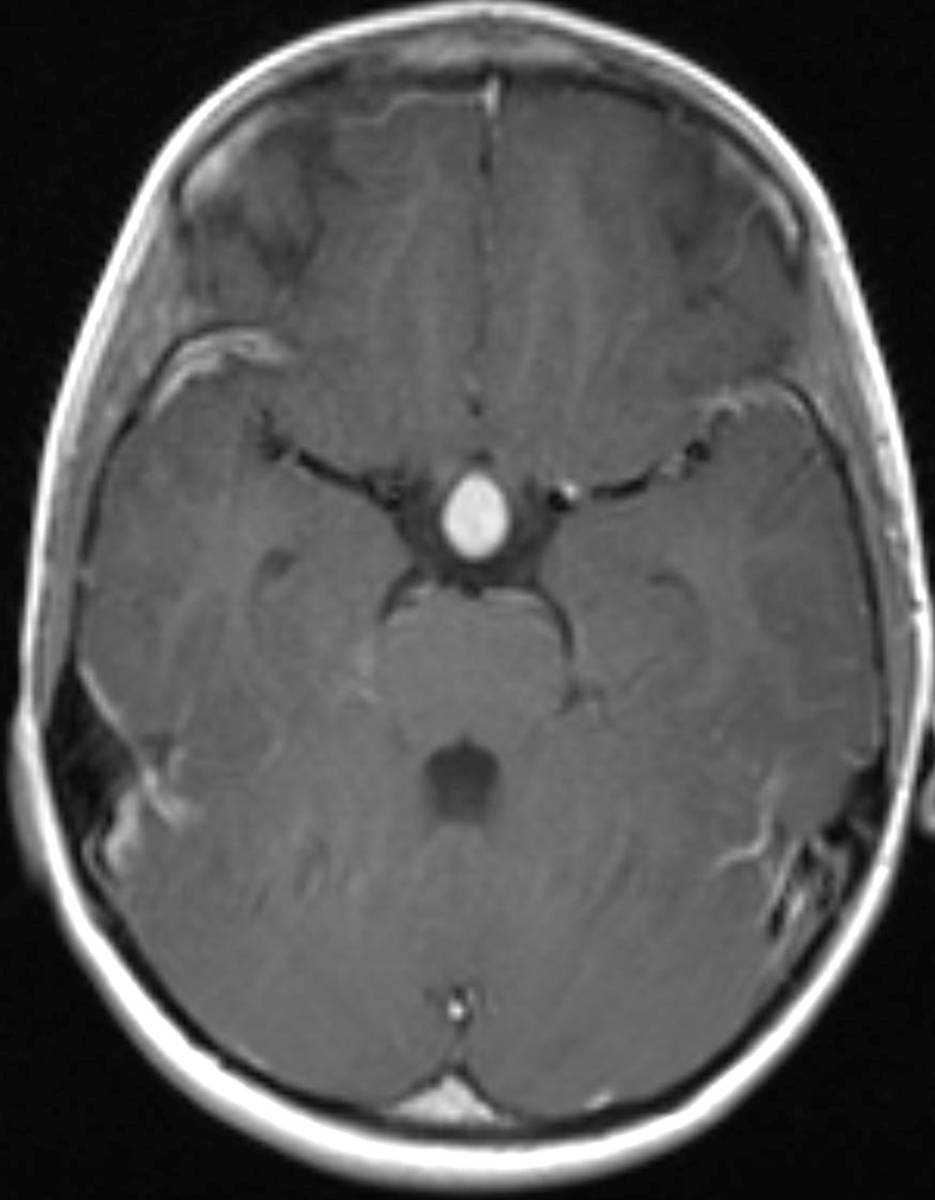

This is a case of Langerhans Cell Histiocytosis, or LCH, of the pituitary gland and infundibulum in a 6-year-old male. The first image is sagittal T1-weighted with some motion degradation. There is thickening of the infundibulum and pituitary gland itself, with classic loss of the typically hyerintense posterior pituitary. The second image is a noncontrast coronal T1 correlate redemonstrating infundibular thickening as well as enlargement of the pituitary gland itself. The third image is with T2 weighting in the coronal plane redemonstrating thickening of the pituitary stalk. The fourth through sixth images are multi planar postcontrast T1-weighted sequences demonstrating avid post contrast enhancement of the markedly enlarged infundibulum and pituitary gland itself. LCH is a reactive clonal disease of the monocyte-macrophage system, and may affect almost any organ system. LCH CNS involvement may fall into one of several forms such as: osseous lesions with or without soft tissue components, intra-cranial extra-axial lesions, such as in the hypothalamic-pituitary region, meninges, or circumventricular organs, intracranial intra-axial lesions and cerebral atrophy. Langerhans cell histiocytosis is the most common cause of infundibular thickening in childhood. Diabetes insipidus is the typical clinical presentation of hypothalamic-pituitary involvement.